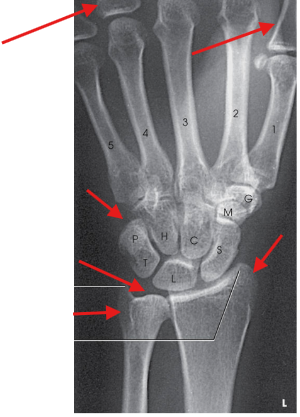

-

A

Distal radius and ulna, carpals, and proximal half of metacarpals

no excessive flexion of digits to overlap and obscure metacarpals

no rotation in carpals, metacarpals, radius, and ulna

open radioulnar joint space